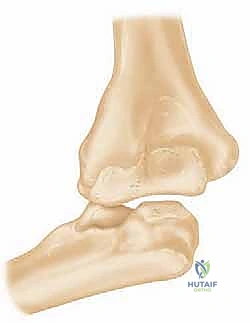

- Dysfunctional Instability of the Elbow: This is a particularly challenging clinical situation where the very fulcrum of stable elbow function has been compromised or lost entirely. Imagine the forearm losing its stable connection to the brachium.

FIG 1 • Radiograph demonstrating dissociation of the forearm from the brachium in a patient with an inadequately treated fracture of the distal humerus with resultant nonunion.

* Chronic Ligamentous Instability (Dislocation): Persistent instability or recurrent dislocation of the elbow, especially in elderly or osteopenic patients, can inevitably lead to progressive articular degeneration. The joint surfaces are constantly grinding and impacting abnormally.